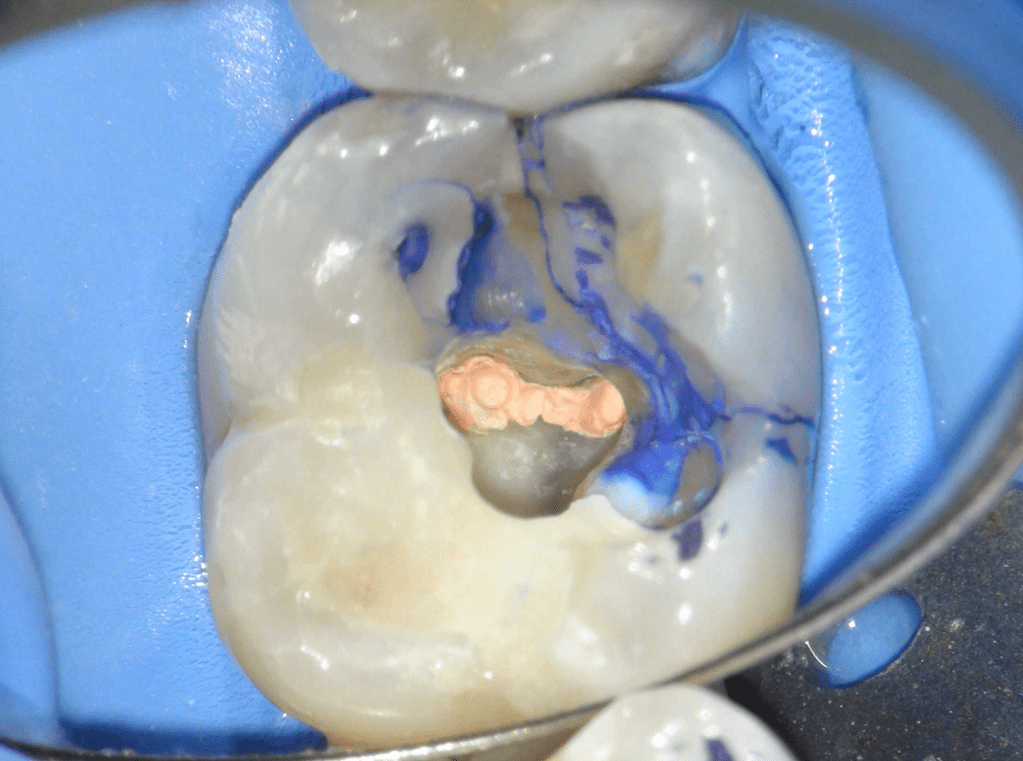

Reco pre-endo gingivectomái, pared yuxtaosea